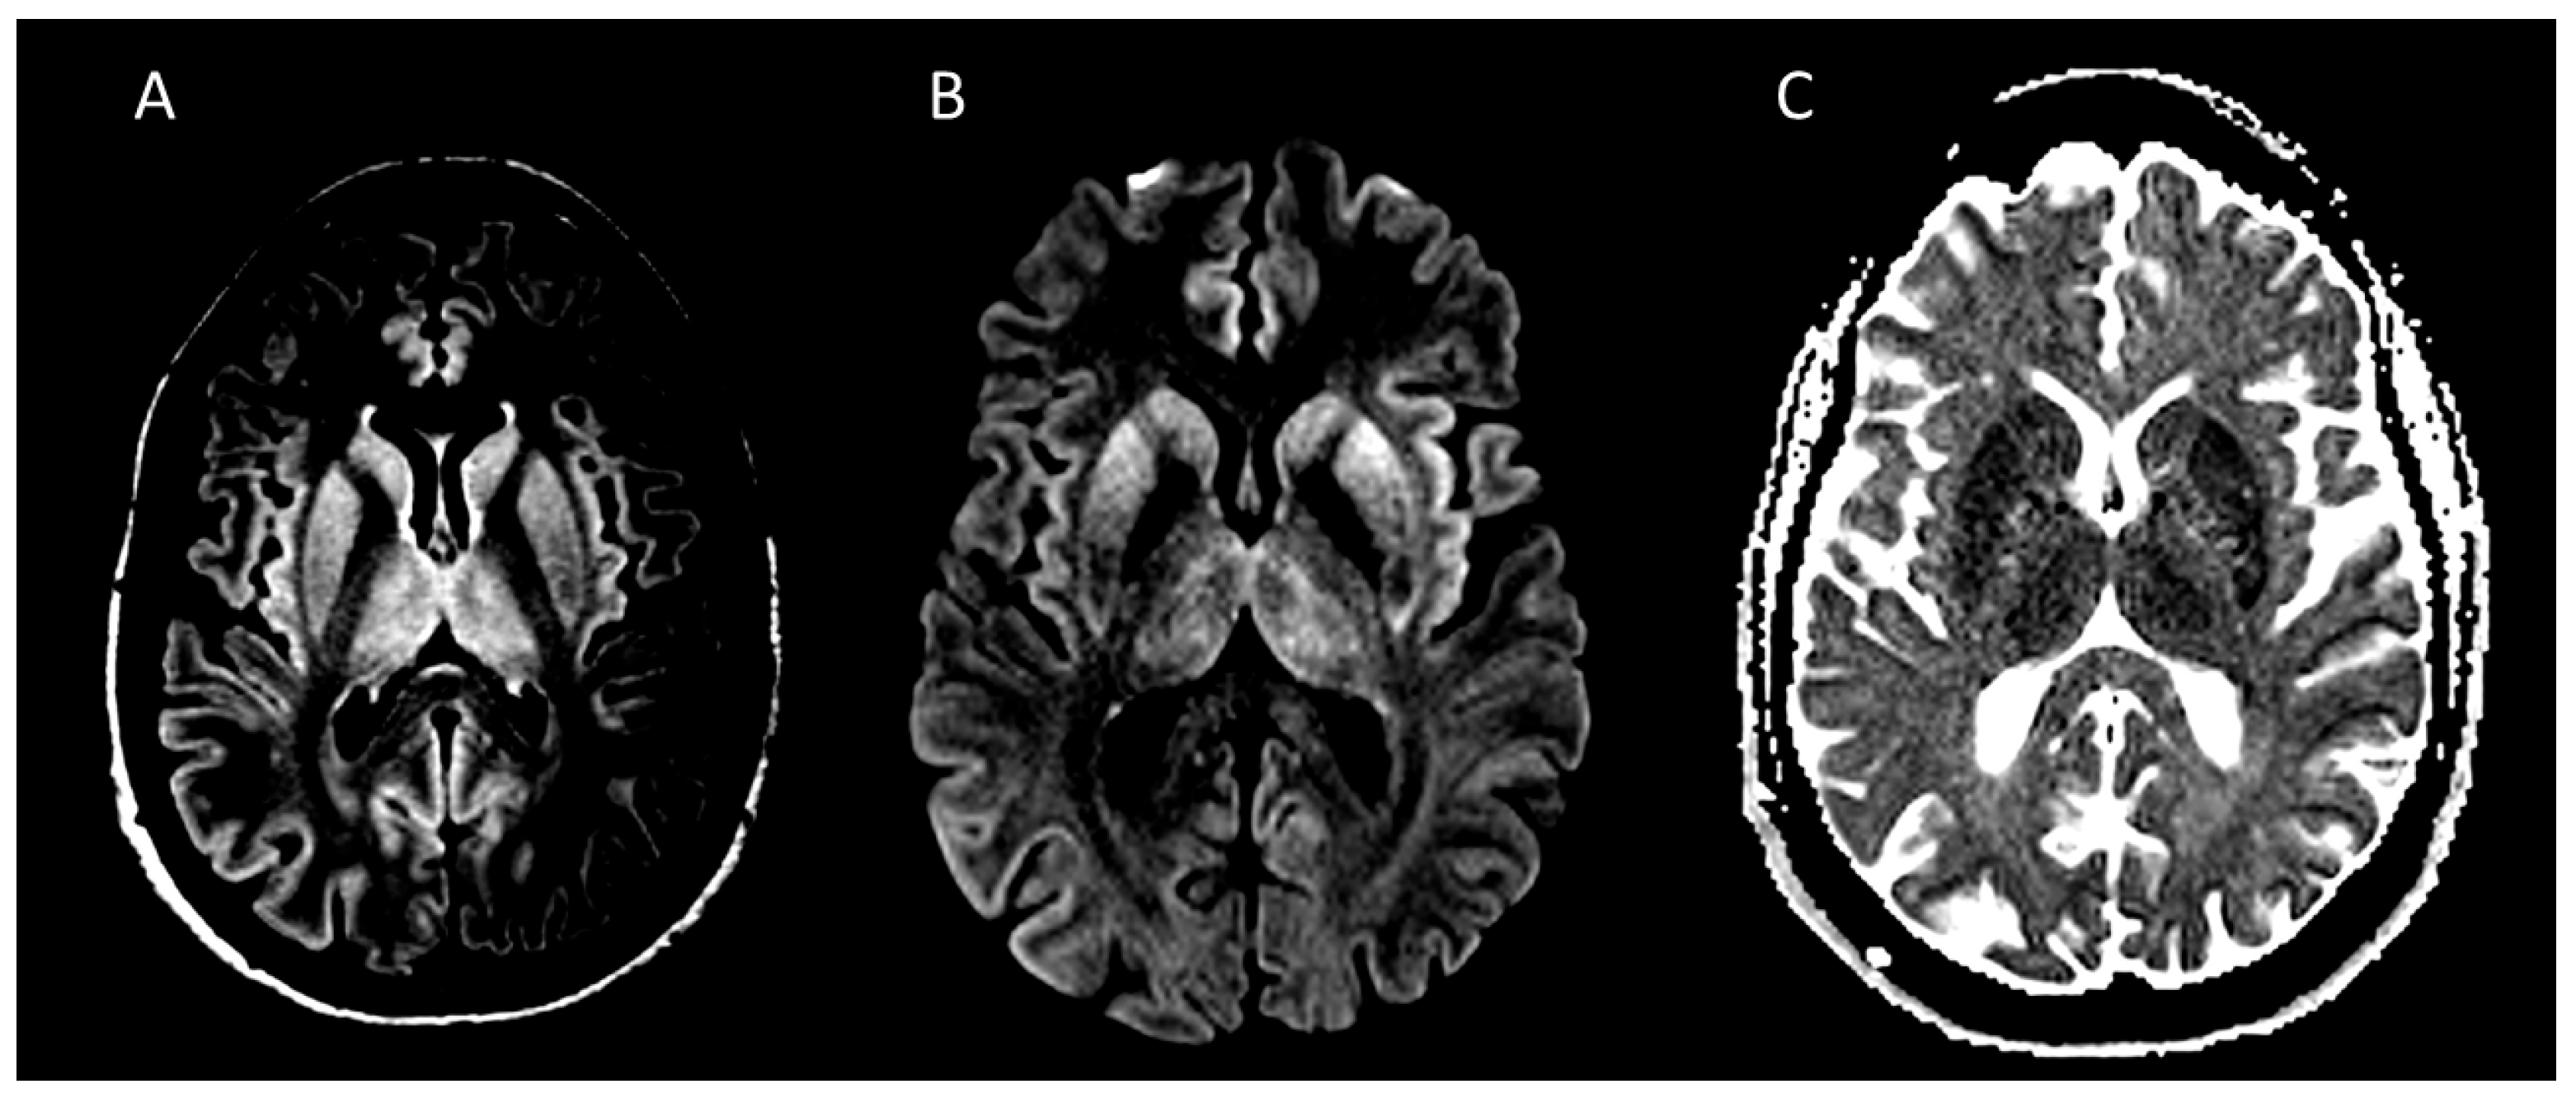

6.1. Neuroimaging